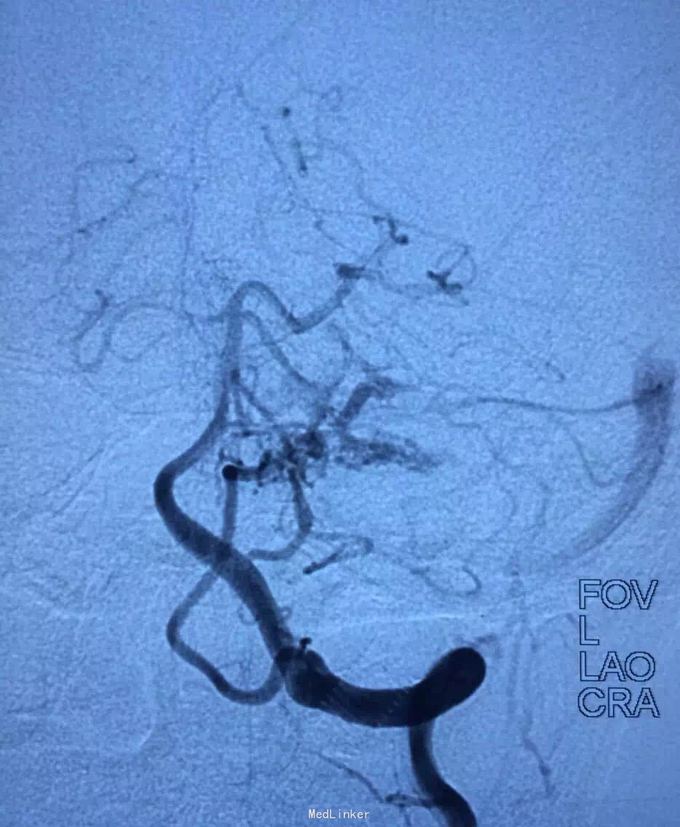

AVM

小脑出血

介入治疗